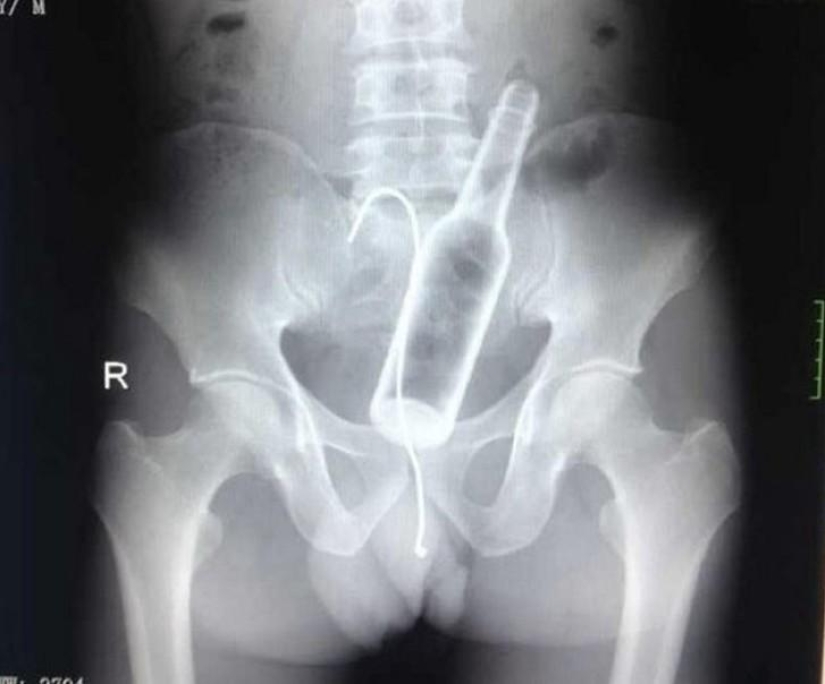

9. Bottle.